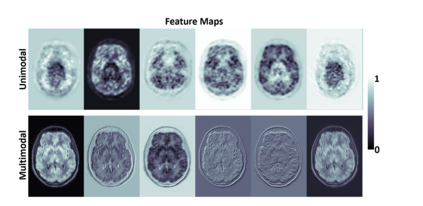

Radiation exposure in positron emission tomography (PET) imaging limits its usage in the studies of radiation-sensitive populations, e.g., pregnant women, children, and adults that require longitudinal imaging. Reducing the PET radiotracer dose or acquisition time reduces photon counts, which can deteriorate image quality. Recent deep-neural-network (DNN) based methods for image-to-image translation enable the mapping of low-quality PET images (acquired using substantially reduced dose), coupled with the associated magnetic resonance imaging (MRI) images, to high-quality PET images. However, such DNN methods focus on applications involving test data that match the statistical characteristics of the training data very closely and give little attention to evaluating the performance of these DNNs on new out-of-distribution (OOD) acquisitions. We propose a novel DNN formulation that models the (i) underlying sinogram-based physics of the PET imaging system and (ii) the uncertainty in the DNN output through the per-voxel heteroscedasticity of the residuals between the predicted and the high-quality reference images. Our sinogram-based uncertainty-aware DNN framework, namely, suDNN, estimates a standard-dose PET image using multimodal input in the form of (i) a low-dose/low-count PET image and (ii) the corresponding multi-contrast MRI images, leading to improved robustness of suDNN to OOD acquisitions. Results on in vivo simultaneous PET-MRI, and various forms of OOD data in PET-MRI, show the benefits of suDNN over the current state of the art, quantitatively and qualitatively.